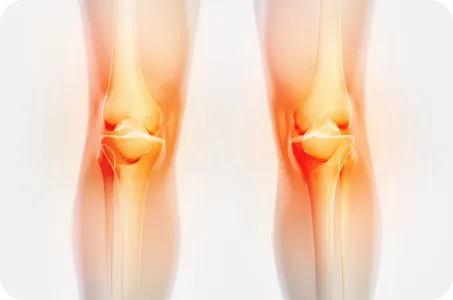

퇴행성 관절염

무릎의 퇴행성 변화로 연골 소실이 이루어져 뼈와 인대 등에 손상이 일어나 염증과 통증이 발생하는 질환으로, 노화에 의해 중년 및 노년에서 흔히 발생하며, 비만 환자나 여성에게도 주로 나타나며, 최근 30~40대 환자에게도 나타납니다.

원인

• 무릎 사용이 과다한 직업군을 가진 경우

• 유전적 요인의 경우

• 반복적인 외상이나 심한 충격으로 인한 경우

• 무릎의 퇴행성 변화로 연골이 닳아진 경우

• 무릎관절의 과다 사용인 경우